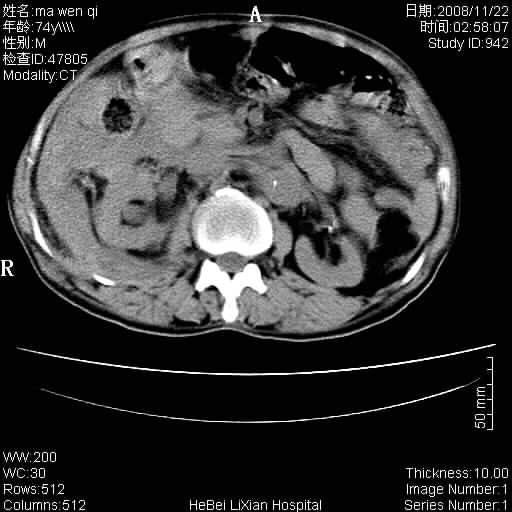

患者男 74岁.突然昏迷,休克6小时.血压70/30,头颅ct未见异常,既往体健.

补充病史,保留导尿10小时,尿袋内只有少许尿液,患者于住院后15小时后去世.

腹主动脉、双侧髂动脉夹层动脉瘤破裂出血进入腹腔。

1)考虑双侧髂动脉瘤并右侧动脉瘤破裂出血,右侧腹膜后及腹腔积血。2)双侧腹股沟疝。

1)考虑,腹主动脉、双侧髂动脉夹层动脉瘤破裂伴右侧腹膜后及腹腔积血。2)双侧腹股沟疝。

1)考虑胸、腹主动脉、双侧髂动脉瘤并右侧动脉瘤破裂出血,右侧腹膜后及腹腔积血。2)双侧腹股沟疝。